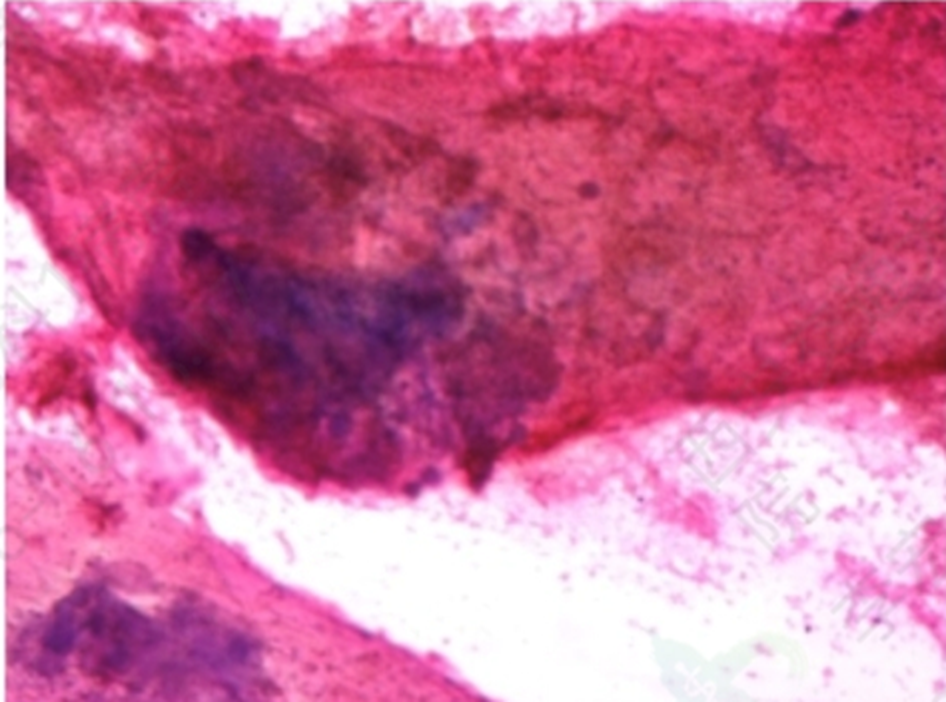

图6 甲状腺细胞镜下

• 左肺穿刺活检示非小细胞癌;免组染色CK7(+)、TTF1(-)、NapsinA(-)、CK5/6(+)、P40(+)、Ki67(+30%)、ALK-D5F3(-)、Her2(0)、C-Met(2+)、PD-L1(TPS:+5%)(Ventana,E1L3N),结合免组标记提示低分化鳞状细胞癌